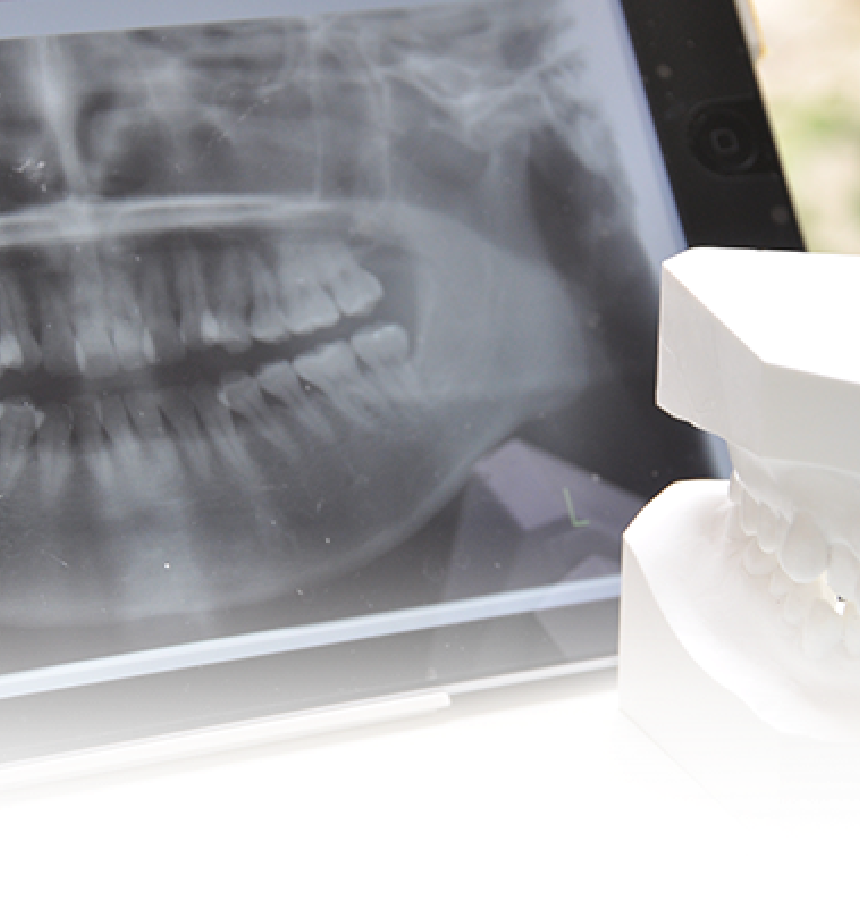

• Comprehensive Diagnosis全顎治療における診査診断最適な治療をご提案